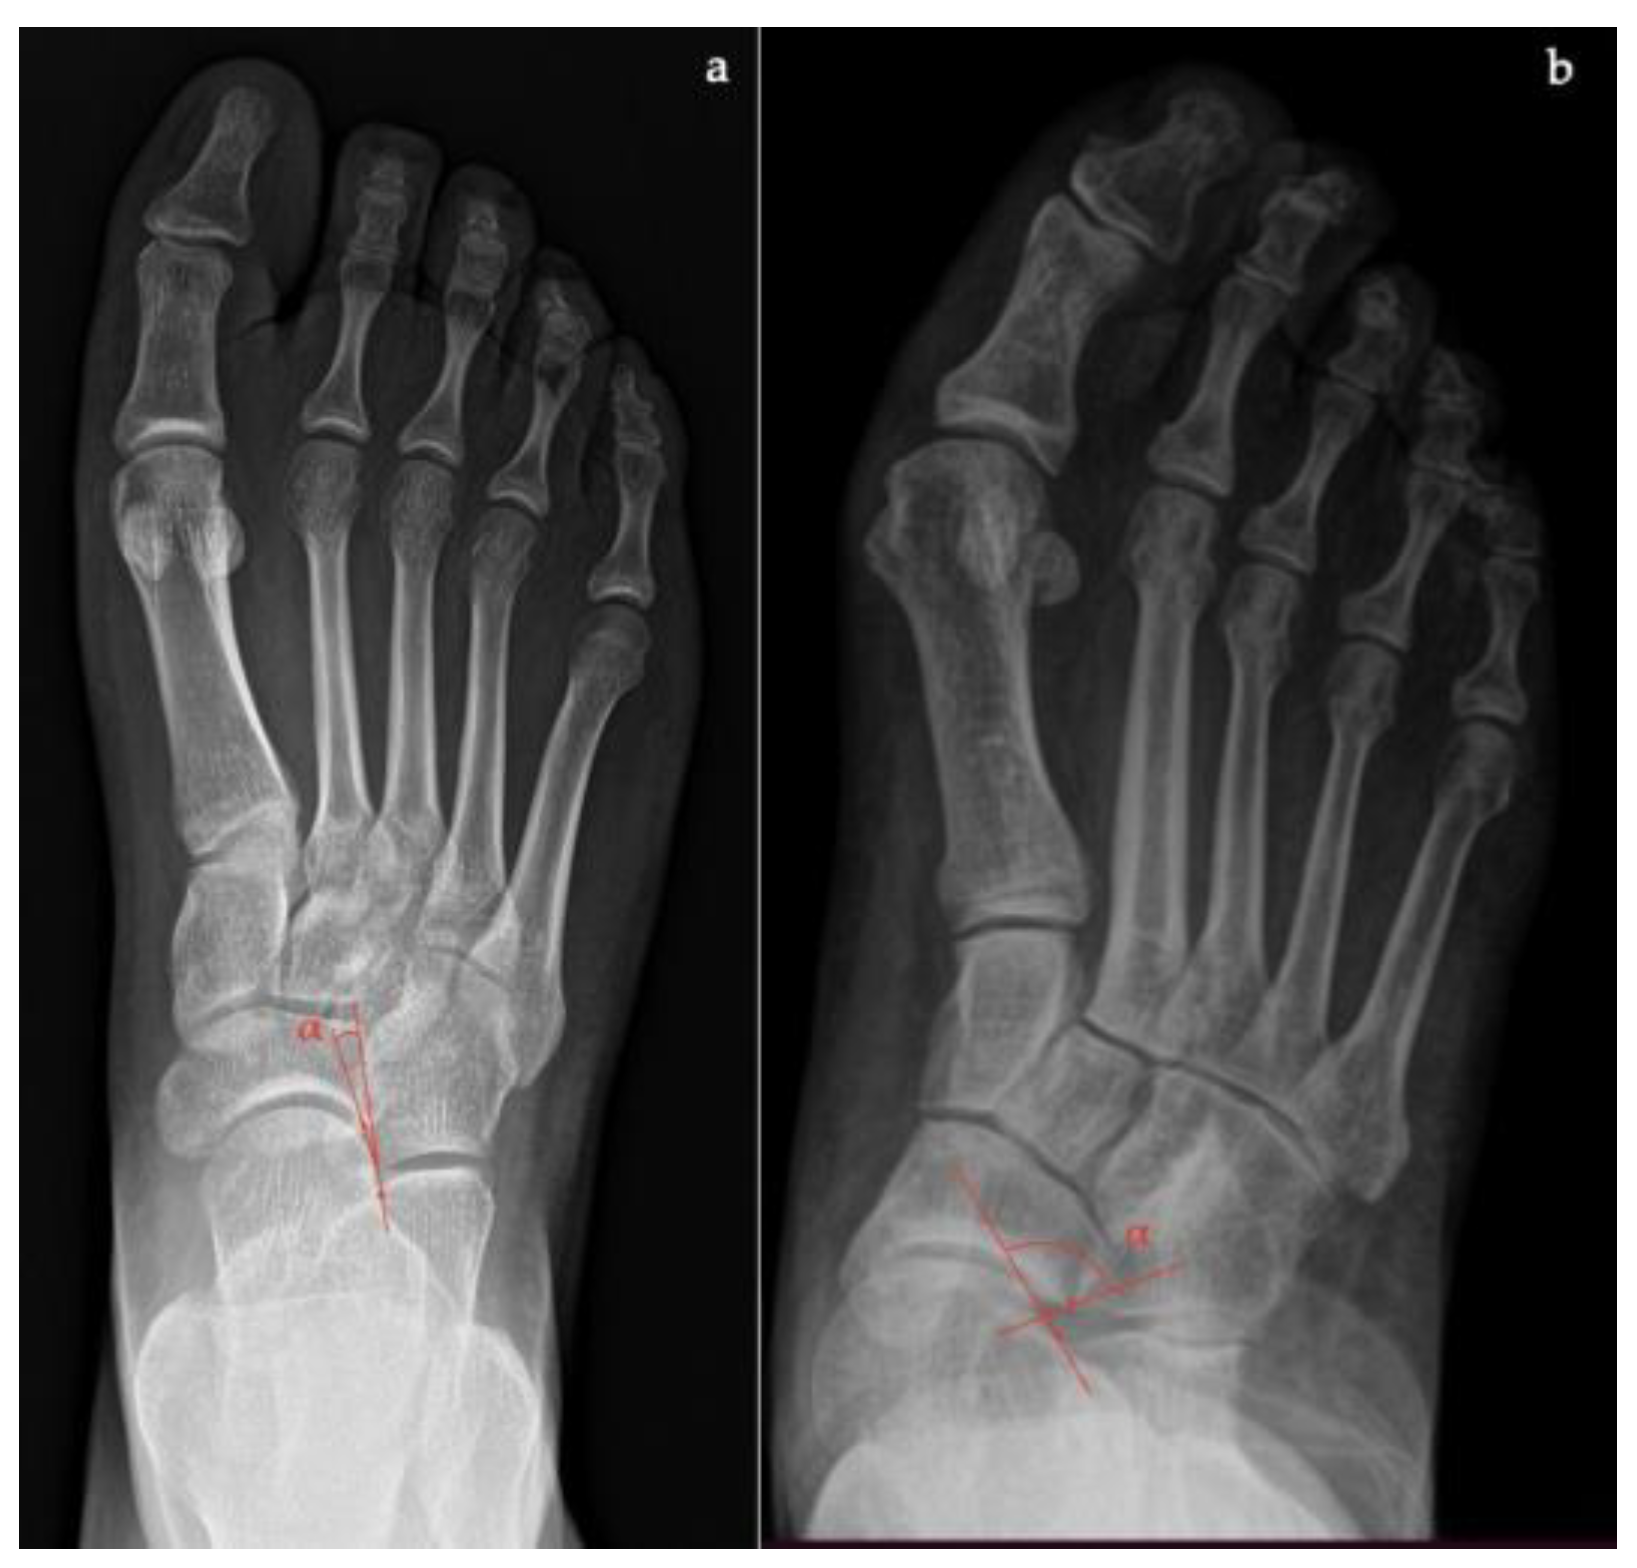

- Talar–first metatarsal angle, between the lines drawn along the long axis of the talus and the first metatarsal (normal 0°, flatfoot: mild >4°, moderate >15°, severe >30°) (Figure 1);

- Talonavicular coverage angle, between the line that joins the medial and lateral articular margins of the talus, and the line that joins the medial and lateral articular margins of the navicular, it represents forefoot abduction (normal, <7°; flatfoot, >7°) (Figure 2);